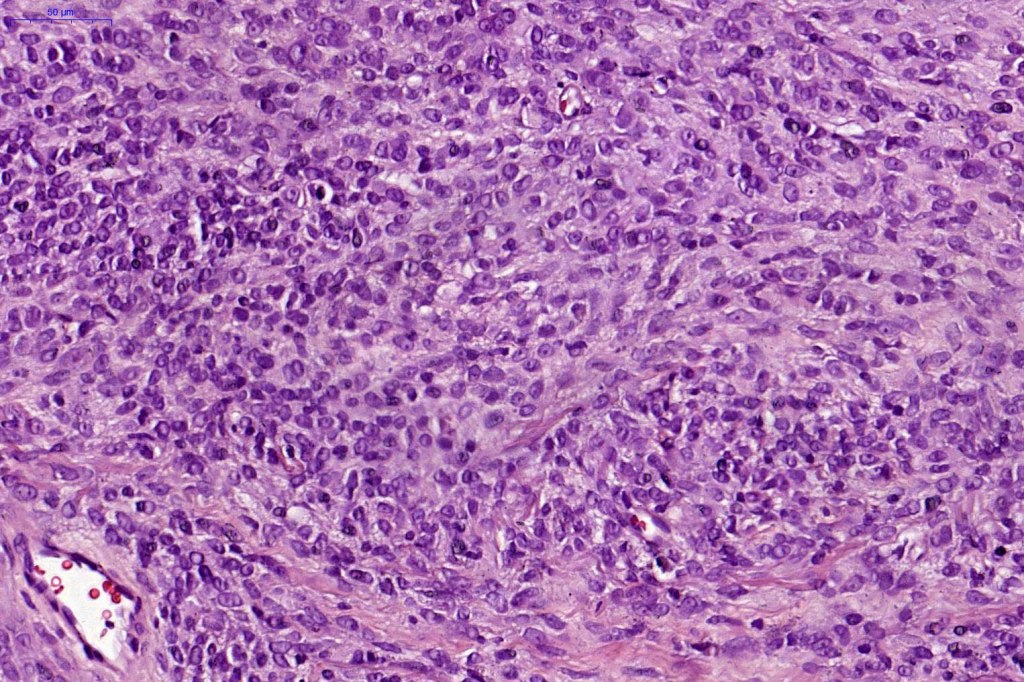

Combined common & deep penetrating nevus